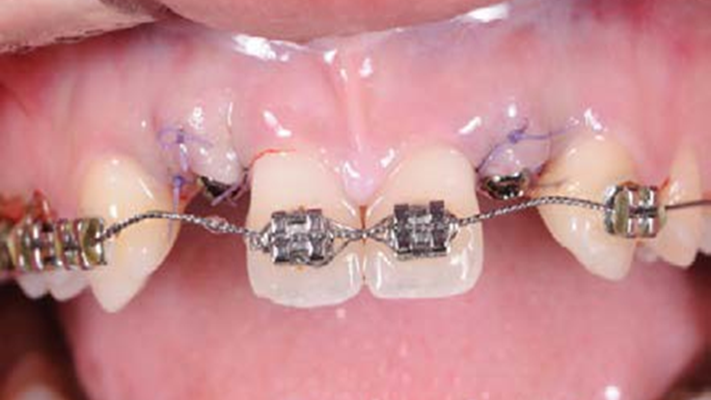

Clinical case: Immediate placement in maxillary anterior narrow space using Advanced Intermezzo

- Courtesy of Dr. Jung Sam Lee, Korea -

Advanced Intermezzo. anterior esthetics, esthetic, provisional restoration, esthetic zone, #13, maxillary anterior, Dr. Jung Sam Lee, anterior aesthetics, aesthetic, aesthetics

Advanced Intermezzo implant system